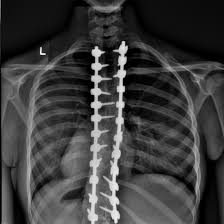

Scoliosis surgery — typically a spinal fusion using rods, screws, and bone grafts — can correct severe curves, but it comes with long-term consequences that patients must understand.

• Stops curve progression in severe cases (typically above 45–50° Cobb angle).

• Improves spinal alignment and overall appearance.

• Loss of flexibility: The fused section no longer bends or twists. Movement like dancing, yoga, or bending to tie shoes becomes restricted.